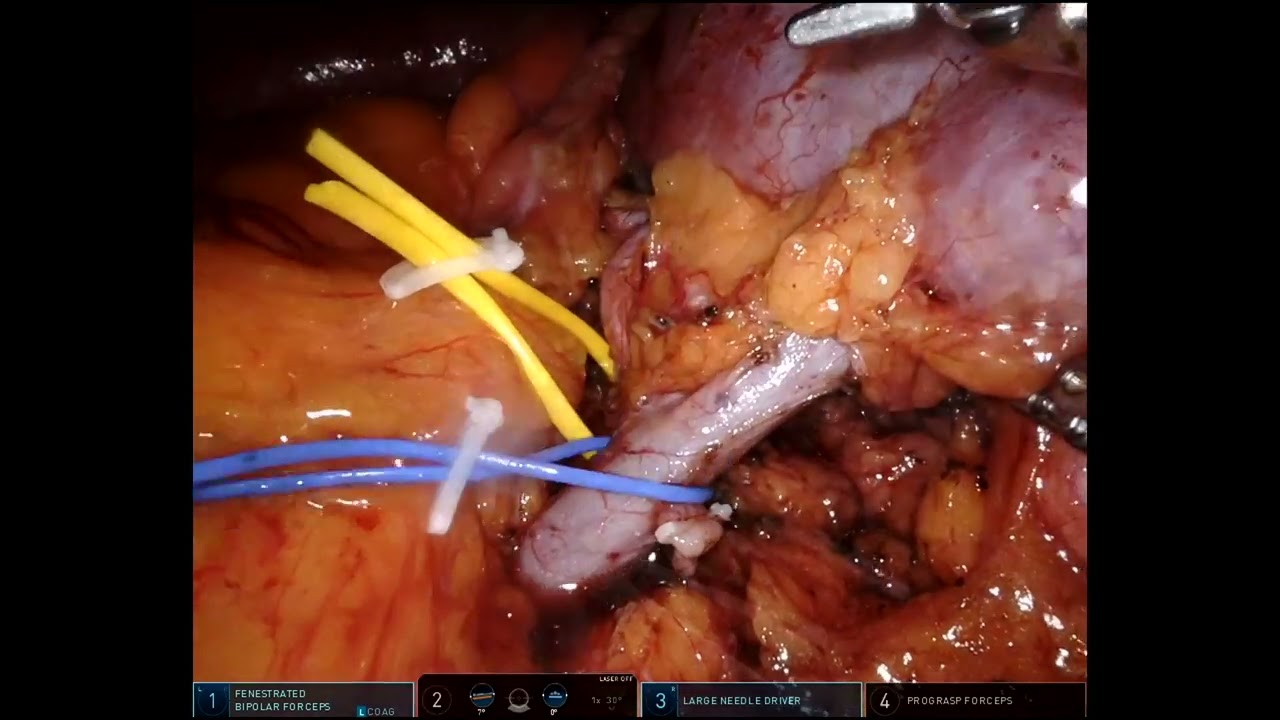

#219 Robot-assisted minimal invasive CABG using bilateral thoracic arteries- Dr. Michiel Algoet

KS Awards, Robotics, Surgeon ';